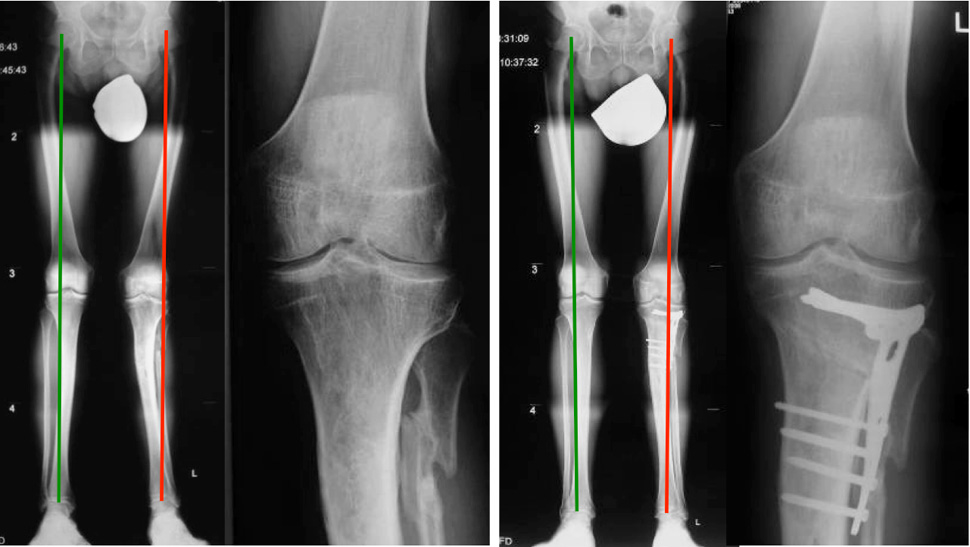

Figure 5

Patient before and after realignment surgery with an open wedge osteotomy of the proximal tibia.

The efficacy of realignment surgery to restore almost normo-biomechanics has been shown to relieve pain and improve function [71]. The orthopaedic procedure includes correction osteotomy, with either open or closing wedge, on the proximal tibia for the knee and on the distal tibia for the ankle, followed by an arthroscopy for cartilage and meniscal surgery, if needed (fig. 5). The shifted and normalised mechanical axis allows addressing the osteochondral lesions with orthobiologics and viscosupplementation [71]. There are a variety of procedures available for the management of OCL’s: the surgeon may treat the articular cartilage, i.e., autologous chondrocytes implantations (ACI), the bone with microfracturing, or both with transplantation of osteochondral allografts (OATS) or mosaicplasty [72, 73]. Lately collaborations with tissue engineering broad the horizons of orthopaedic researchers with synthetic scaffolds like autologous osteochondral plugs [74].